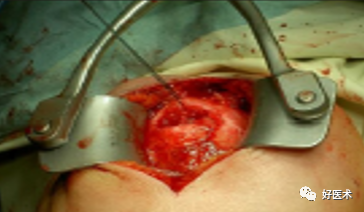

附:大结节撕脱骨折内固定

适用经手法复位失败,骨折移位超过1cm者;骨折块拉至肩峰下。

麻醉:颈丛麻醉 。

体位:仰卧位,患肩垫高与手术台成30°角。

操作方法:

切口:自肩峰外侧缘,约5cm,平行于三角纤维方向。

劈开三角肌纤维,切开三角肌肩峰和锁骨外侧端的附着点,显露结节部

在结节上用3.0钻头朝肱骨头方向钻孔,深约12-20mm

用钛丝穿过肩袖

将钛丝缠绕螺钉钉帽一圈

选择合适长度螺钉

拧入干预螺钉至钉帽外露3mm深度

用钢丝钳把钛丝缠绕拧紧,检查骨折复位情况

冲洗伤口,逐层缝合肌肉,皮肤切口

曲肘90°位三角巾悬吊制动,2周后开始被动活动